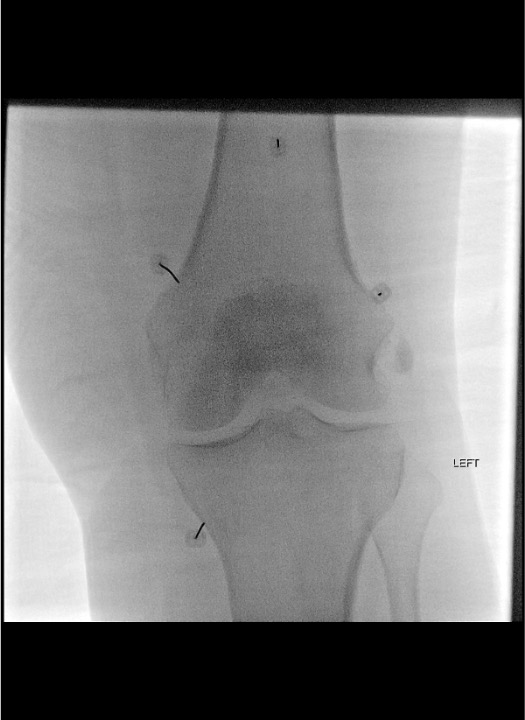

Target Localization by View

| Target Nerve | AP View Landmark | Lateral View Confirmation | Key Pitfall |

|---|---|---|---|

| Superior Medial Genicular (SMG) | Medial femur โ center of the "notch" between the femoral shaft and medial femoral condyle (metaphyseal junction) | Mid-depth of condyle; not anterior capsule, not posterior | Too posterior โ saphenous nerve โ medial numbness |

| Superior Lateral Genicular (SLG) | Lateral femur โ analogous junction of lateral femoral shaft and lateral femoral condyle | Mid-depth of condyle laterally | Too lateral/inferior โ peroneal nerve โ foot drop risk |

| Inferior Medial Genicular (IMG) | Medial tibia โ junction of medial tibial shaft and medial tibial condyle, just distal to the medial joint line | Anterior to fibular head level, mid-depth of tibial condyle | Most commonly missed target โ ensure cannula is distal enough |

AP View Essentials

- All three metaphyseal junctions are visible on a single AP view of the knee

- SMG and IMG are on the medial side; SLG on the lateral side

- The RF cannula tip should overlay the periosteum at the junction โ not on the joint space, not on the shaft alone

- Confirm position at each of the three sites before moving to lateral confirmation